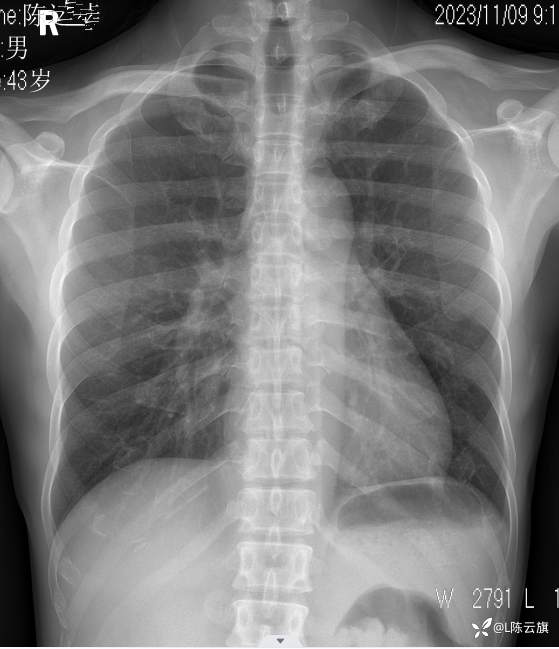

胸片4: